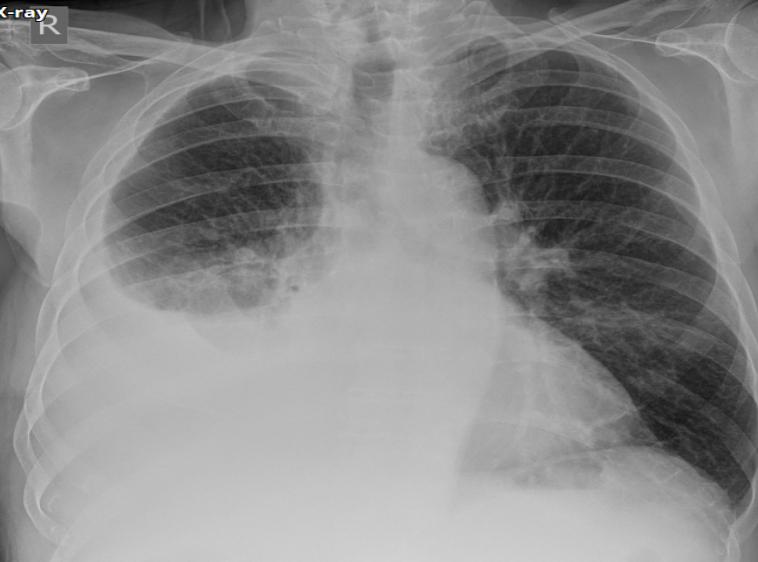

PA chest X-ray

Opacity on right side

Miniscus sign (indicates pleural effusion in PA view)

AP chest X-ray

Grading sign (indicates pleural effusion in AP view)